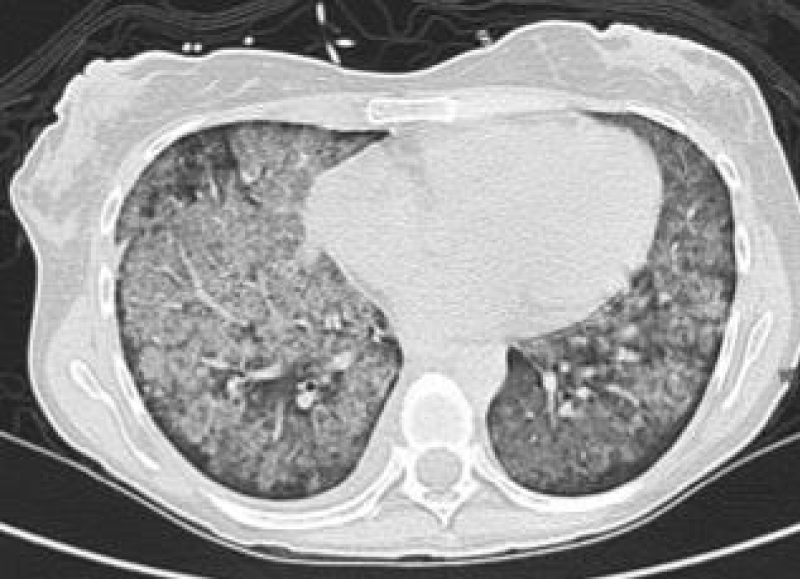

A 29 year old serving soldier was admitted with complains of fever, pain abdomen, hemoptysis, bodyache and dark coloured urine since 03 days. On admission patient was tachypneic and hypotensive. Blood investigations revealed decrease hemoglobin and platelet count. pANCA came out to be positive. CT scan was suggestive of bilateral nodular densities and x ray showed bilateral fluffy opacities. Despite management with oxygenation, iv fluids and iv antibiotics, there was no improvement in his symptoms and his condition further deteriorated. Bronchoscopy revealed diffuse bronchoalveolar hemorrhage. Biochemical evaluation revealed deranged kidney and liver function test. Patient on ventilation developed bradycardia, hypotension and desaturation. On examination blood pressure was not recordable, carotid pulse was not recordable, CPR was started and patient was declared dead at 1215hrs on 30 Oct 2020 Figures 1,2.

Figure 1: X Ray shows bilateral fluffy opacities.